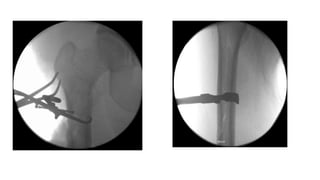

Punto de Entrada

• Error:

• Muy anterior y muy

lateral

• Si usa un clavo de

inicio trocantérico:

• Comienze medial a

la punta del

trocánter mayor

• Creara valgo

• Si usa un clavo de inicio

trocantérico:

• Comienze central o incluso

posterior en el trocánter

mayor

• Luchará contra la flexión del

fragmento proximal.

• Si se usa clavo piriforme:

• Punto de inicio en línea con

la vía intramedular en el

segmento distal

• El punto de partida ya es

medial y posterior.

Core Curriculum V5